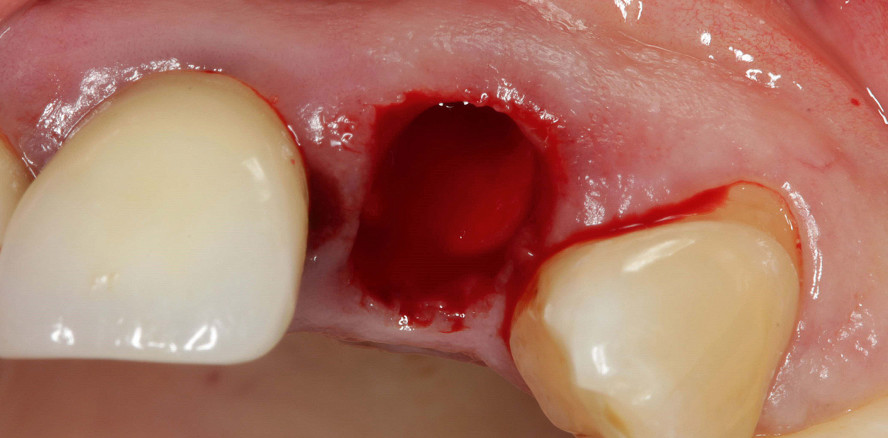

Nach der schonenden Extraktion (Abb. 3) wurde eine Socket Preservation durchgeführt. Das Koagel wurde dabei durch den Soft Tissue Punch geschützt. Es erfolgte die Entnahme eines vollen Weichgewebstransplantats aus dem Tuberbereich (Abb. 4). Das Transplantat wurde im bindegewebigen Bereich längs geteilt, sodass es flügelartig aufgeklappt werden konnte (Abb. 5). Das Empfängerbett wurde tunnelierend nach palatinal und bukkal zur Aufnahme der bindegewebigen Flügel des Transplantats präpariert. Zum einen konnte das Transplantat mithilfe der Flügel leichter in Sollposition adaptiert und durch Nähte fixiert werden (Abb. 6), und zum anderen erleichterte es die Revaskularisierung im Empfängerbett.